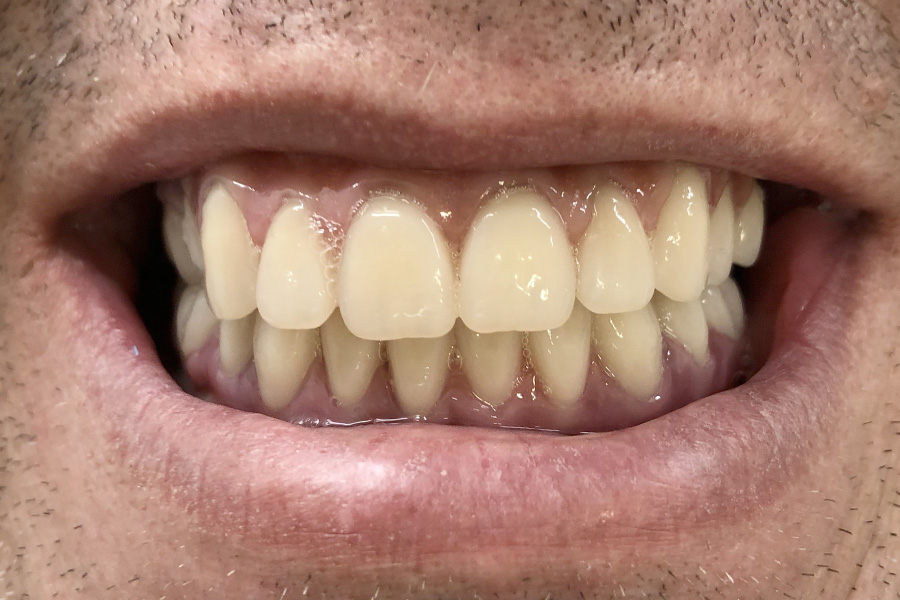

Phil was wearing a removable partial denture for many years.

As he lost some more teeth the pasrtial denture became less stable. Chris finally decided to have dental implants his missing teeth.

Two implants were utilised to support a bridge where there were three missing teeth in a row. His existing natural teeth received crowns and veneers as reinforcements and also to match the highly esthetic implant crowns and bridges.